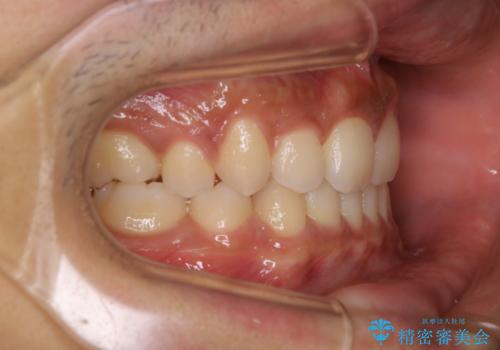

インビザライン単独でここまでできる!!抜歯矯正

- 治療計画

1日20時間以上、正しくインビザラインを使用して頂いたおかげで、ワイヤーに切り替えることなく矯正治療を終了することが出来ました。周囲からも歯並びがすごく綺麗になったと言われたのことで大変ご満足いただけました。